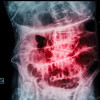

Dok saya ada dapat px UGD dgn keluhan nyeri perut VAS 2-3, tidak bisa bab 2 hari terakhir dan tidak bisa kentut. Setelah di BNO 3 posisi tampak gambaran ileus. Namun pasien kondisi TTV stabil, bahkan bisa duduk dan berjalan. Oleh dpjp px kemudian rawat jalan pulang besok tanpa tindakan op. Apakah px dgn ileus obstruksi selalu indikasi utk op cito ya dok? apakah ada istilahnya ileus stabil dok? terapi yg bisa kita berikan pada kasus ileus yg kondisinya stabil seperti itu?